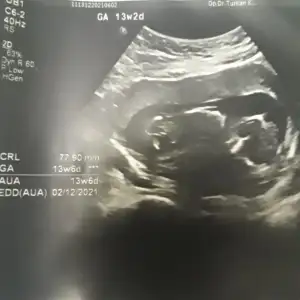

Merhabalar bizimde bebeğimiz 12 haftalarda yorumlarsanız çok sevinirim Ikra meyra Ikra meyra

dr soylemeden siz gorun genital nub teorisi ( bebegin cinsiyeti)

Nuba göre kız mı erkek mi sizce kızlar?